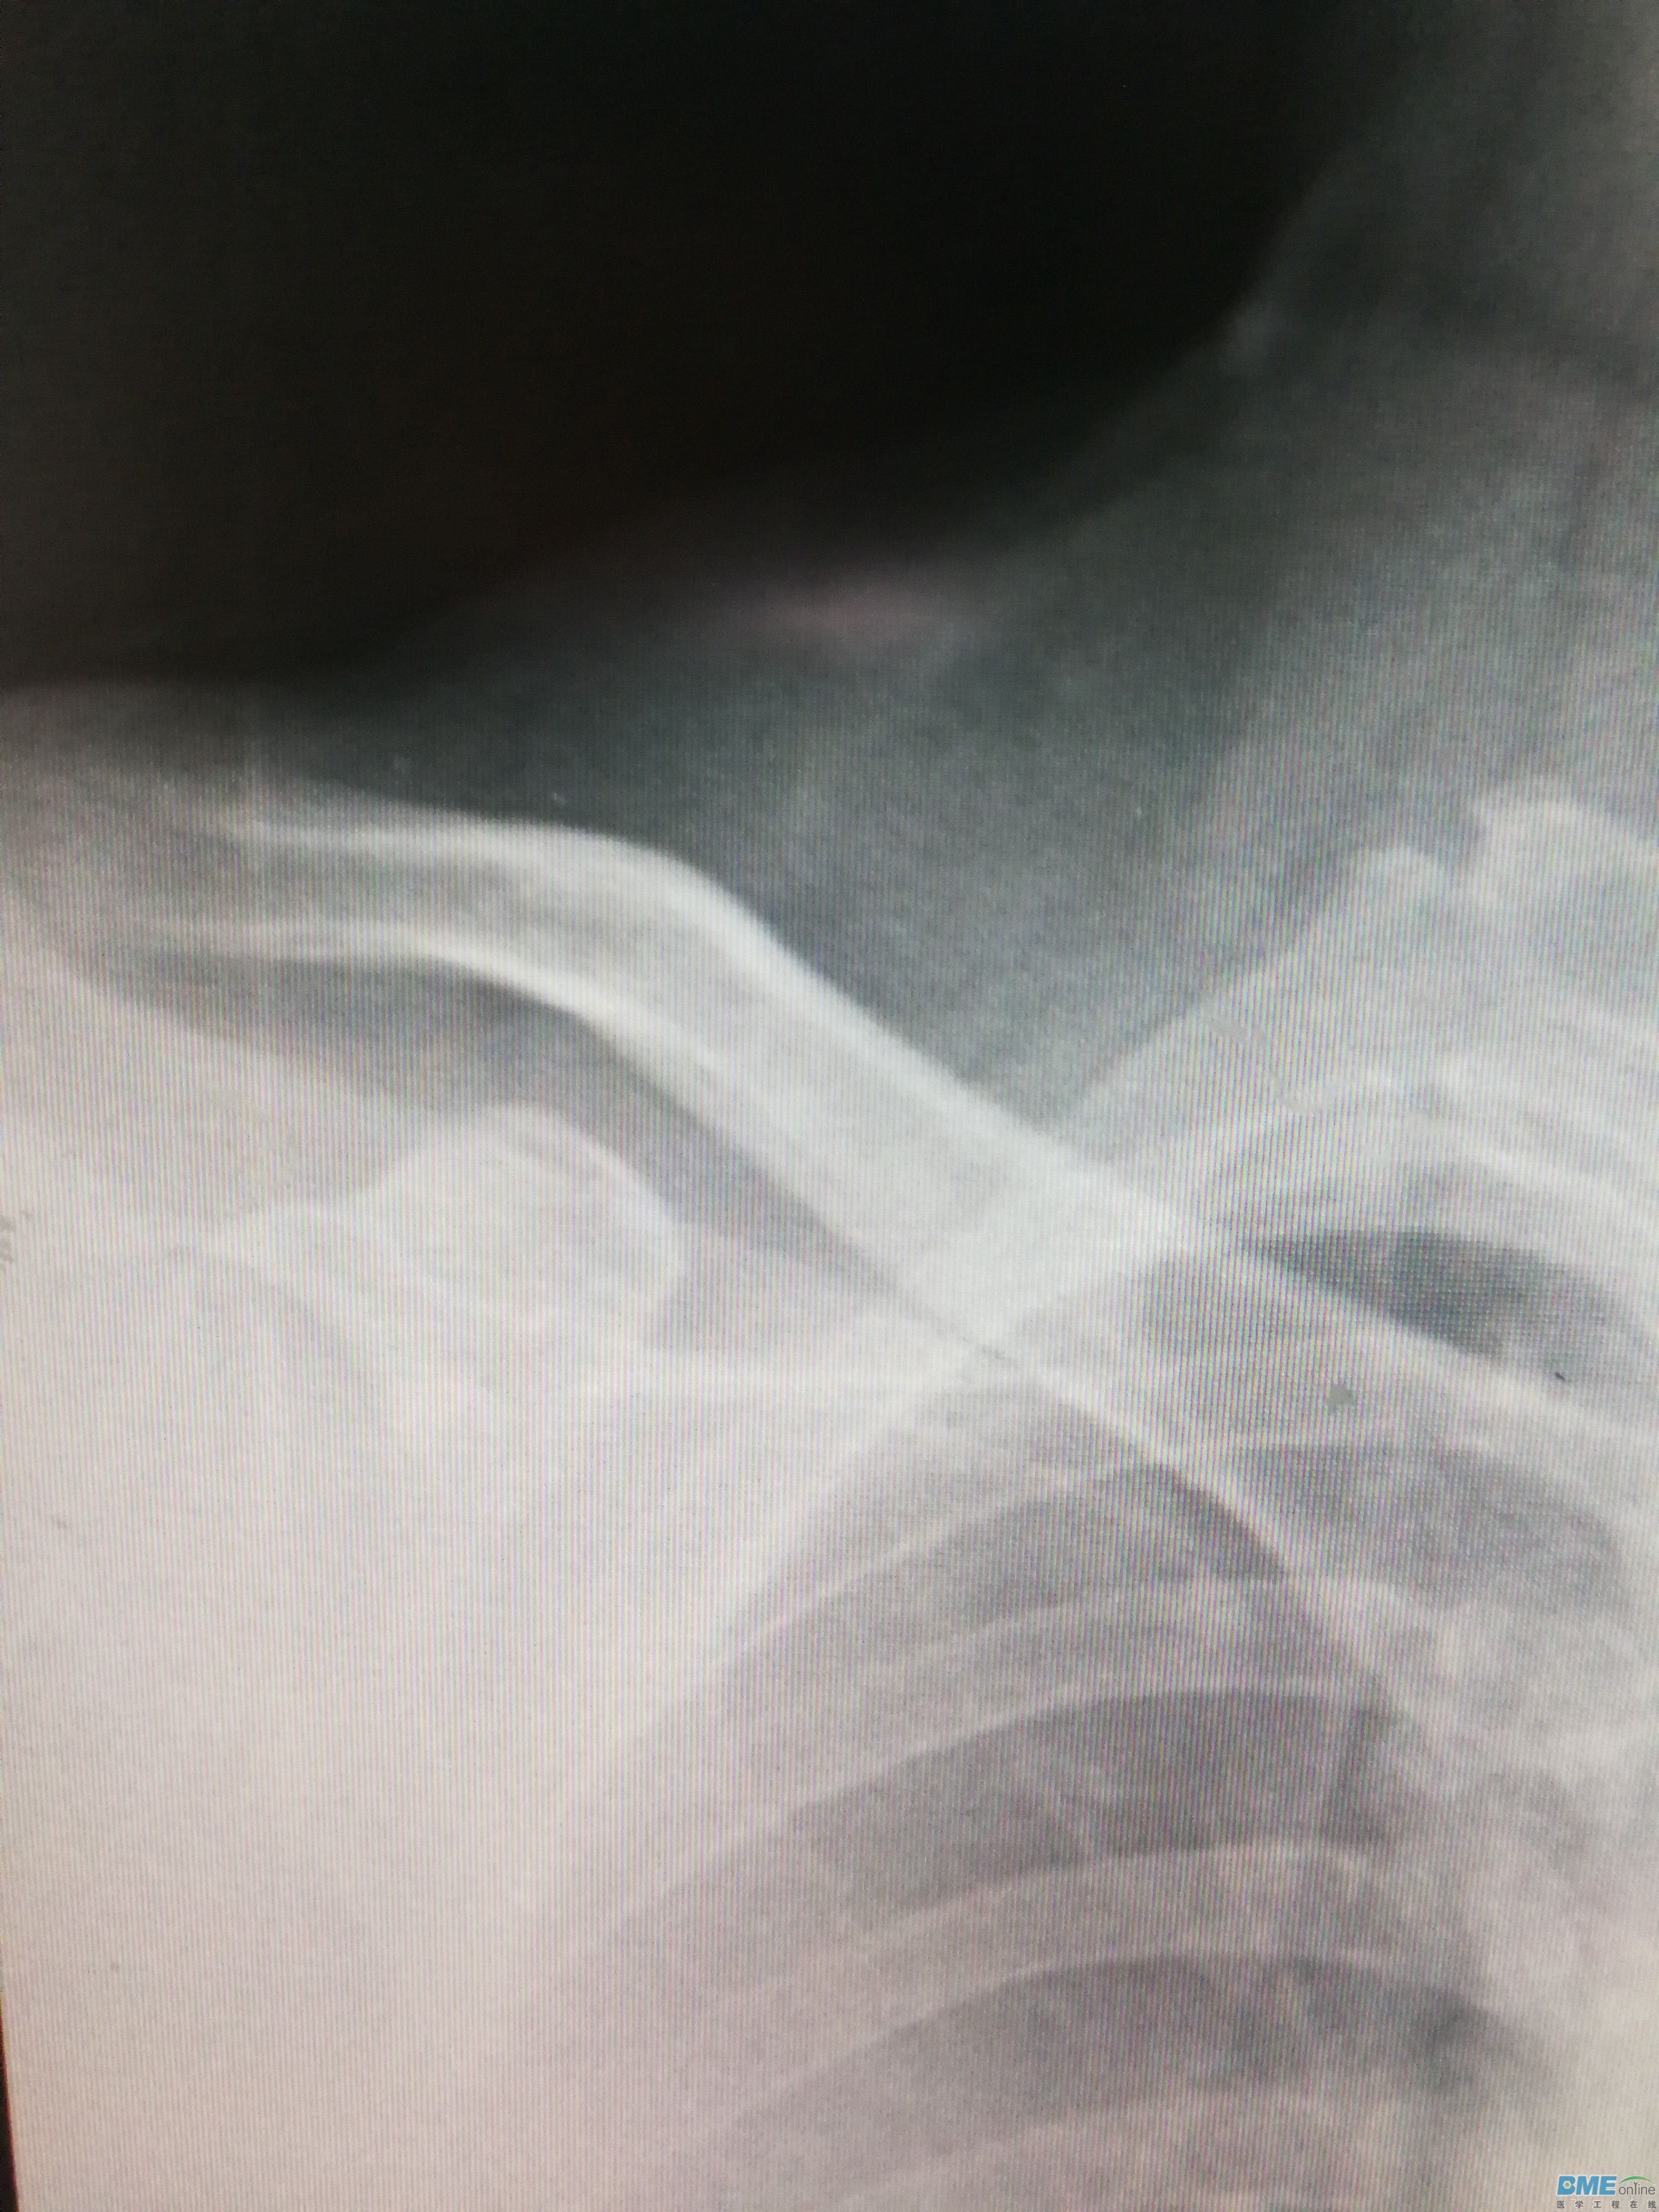

柯达IP影像板出现一条粗细相同的白色伪影该怎么处理?这个IP板还有补救办法吗?

可能是IP板上有灰尘或划痕,用酒精擦一下,应该会好些